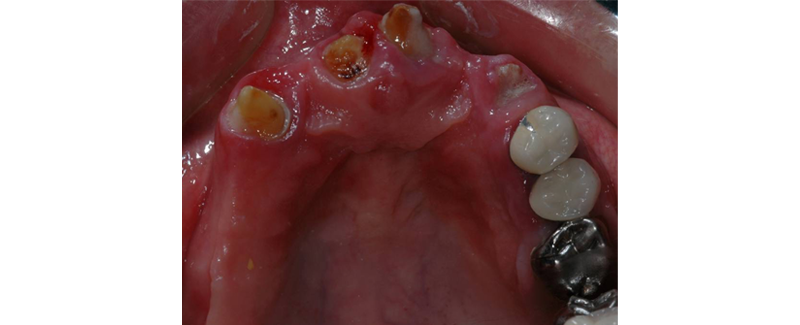

1. Advanced structural damage (Fig. 1)